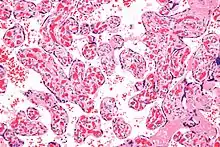

Micrograph of a chorangiosis. H&E stain. | |

Chorangiosis is a placental pathology characterized by an abundance of blood vessels within the chorionic villi.

It is diagnosed by a microscopic examination of the placenta.

Commonly used criteria from Altshuler[2][3] are: "a minimum of 10 villi, each with 10 or more vascular channels, in 10 or more areas of 3 or more random, non-infarcted placental areas when using a ×10 ocular." The Altshuler criteria are not theoretically rigorous, as they do not define the area. Normal villi have up to five vascular channels.[3]